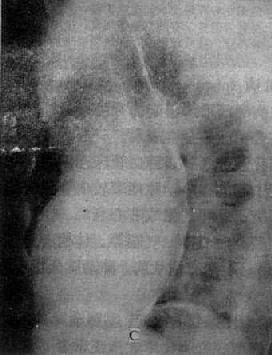

慢性肺原性心脏病

图3-2-17 慢性肺原性心脏病

心呈二尖瓣型,右心室增大,肺动脉突出,但无左心耳增大。肺动脉扩张,尤以右下肺动脉为明显,有肺门截断现象,说明有肺动脉高压肺纹理增强,肺透明度增加,膈平而低,说明有慢性支气管炎肺气肿